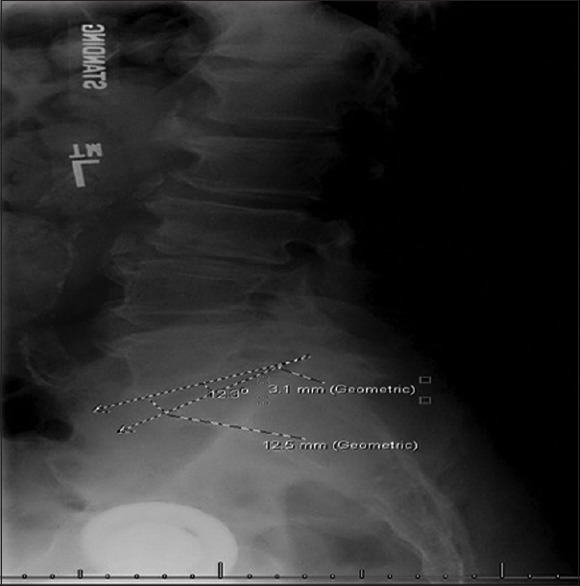

Methods: We retrospectively reviewed patients ≥18 years who underwent TLIF at L5-S1 between January 2015 and September 2023. Patients were grouped by cage type (expandable vs. static). Radiographic data included anterior and posterior disc heights, disc angle, L5-S1, L4-S1, and L1-S1 sagittal lordotic angles, and lumbar distribution index. Measurements were recorded preoperatively and at two postoperative intervals.

Results: A total of 43 patients were analyzed (15 expandable, 28 static). At baseline, the expandable group had greater posterior disc height (5.03 mm vs. 3.06 mm, P < 0.001). At first follow-up, expandable cages showed higher anterior disc height (18.86 mm vs. 11.80 mm, P < 0.001), posterior disc height (7.80 mm vs. 5.30 mm, P < 0.001), and disc angle (16.27° vs. 11.82°, P = 0.040). From preoperative to final follow-up, expandable cages had greater gains in anterior disc height (9.22 mm vs. 3.27 mm, P < 0.001), disc angle (7.84° vs. 0.24°, P = 0.002), and L5-S1 lordosis (7.03° vs. 0.81°, P = 0.012).